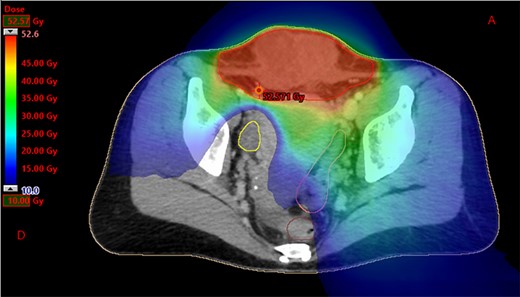

Dosimetry with helicoidal tomotherapy. We can observe the delivered doses from 10 to 52.6 Gy, sparing the right ovary.

We present the case of a 44-year-old woman with no previous history of endometriosis, cancer or other relevant medical condition. She had two cesarean deliveries by a Pfannenstiel incision in 2004 and 2014. In May 2018, the patient presented a subcutaneous abdominal wall mass. The ultrasound described a 2-cm nodule compatible with an endometrioma developed on cesarean section scar. From January 2019, the patient reported a rapidly growing and painful mass, and the abdominal ultrasound confirmed a 45-mm well-defined mass showing acoustic enhancement with diffuse ground-glass echoes (Fig. 1A). The pelvic magnetic resonance imaging (MRI) confirmed an infiltrative heterogeneous lesion measuring 5 cm arising from the Pfannenstiel incision and partially involving rectus abdominis muscles (Fig. 1B,D,F). The MRI did not evidence other signs of pelvic or extra-pelvic endometriosis. The patient was referred to our comprehensive cancer center. Physical examination revealed an abdominal wall mass on the cesarean section scar, measuring around 6 cm (Fig. 2A). No abnormal findings were observed in pelvic examination. The ultrasound-guided biopsy revealed a clear cell carcinoma. Microscopic examination showed a malignant proliferation with glandular, nested and focal papillary patterns. Tumor cells had clear cytoplasm, with hyperchromatic nuclei and hobnail feature (Fig. 3I-A,B,C). They were strongly immunoreactive for CK7, PAX8 and HNF-1β (Fig. 3I-D,E). They were negative for calretinin, CK20, CK5/6, WT1, ER and PR. There was a wild-type pattern with anti-p53 antibody (weak and heterogeneous positivity) (Fig. 3I-F). A hysteroscopy and curettage showed a normal endometrium. Computed tomography of the chest, abdomen and pelvis did not evidence distant metastasis. After discussion at the tumor board, neoadjuvant radiation therapy before surgical excision was recommended due to rapid and extensive local progression. From March 2019 to May 2019, 50 Gy was delivered in 25 fractions to the abdominal wall tumor with helicoidal intensity-modulated radiation therapy (IMRT) using Tomotherapy® (Fig. 4). We tried to spare the right ovary from the irradiation fields, delivering a maximum dose of 5 Gy and a mean dose of 3.9 Gy. In June 2019, a wide surgical excision of the lesion (Fig. 3II) and abdominal wall reconstruction using a biological mesh, as well as total hysterectomy and bilateral salpingectomy, were performed. A careful inspection of abdominopelvic cavity was done during surgery, and no signs of endometriosis were found. Both ovaries were macroscopically normal.